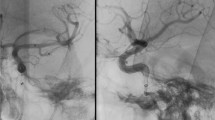

The reviewers were asked two measure the stenosis grade on 2-D DSA series and on MPR and MIP images of i.v. FD-CTA (Fig. 2). The stenosis grade was calculated using the following equation: percentage stenosis = (1-(D stenosis/D normal) X 100. D stenosis is the diameter at its most severe site. D normal is the diameter of the proximal stent [14] (Fig. 2).

The measurement method is displayed in a, b and c (patient 2). Stenosis of the V4 segment is visible (a, DSA). The MIP reconstruction of the subtracted FD-CTA (b) displays the stenosis nicely. MPR reconstruction (c) demonstrates perfusion of the lumen of the stent. This case represents RS. The mean stenosis grade in 8 out of 12 patients measured on DSA, MIP and MPR images (d) concerning each patient is shown. The measurements are nearly identical in all three techniques

Measurements of the stenosis (8 out of 12 patients) showed a mean stenosis of 41.6% (±8.3) in angiography, 48.4% (±9.7) in FD-CT MPR and of 42.1% (±10.1) in FD-CT MIP. Correlation coefficients were: DSA/ FD-CT MIP 0.91, DSA/ FD-CT MPR 0.82 and FD-CT MIP/ FD-CT MPR 0.8. Wilcoxon’s test showed no significant differences between the methods (p > 0.05). An overview of the results from each patient with RS or ISR is displayed in Fig. 2.